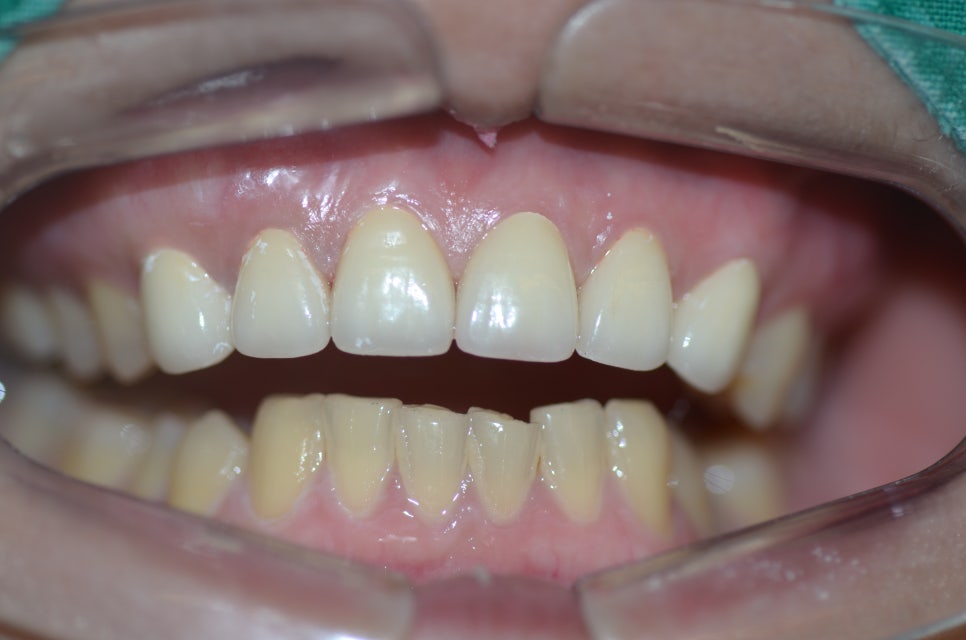

지르코니아 를 올린 모습입니다.

자연스럽게 예쁘게 색깔이 들어갔습니다.

웃을때 아랫니가 많이 보이지 않으시는 경우

보통 송곳니 에서 송곳니까지 6개의 치아를 진행하는 경우가 많습니다.